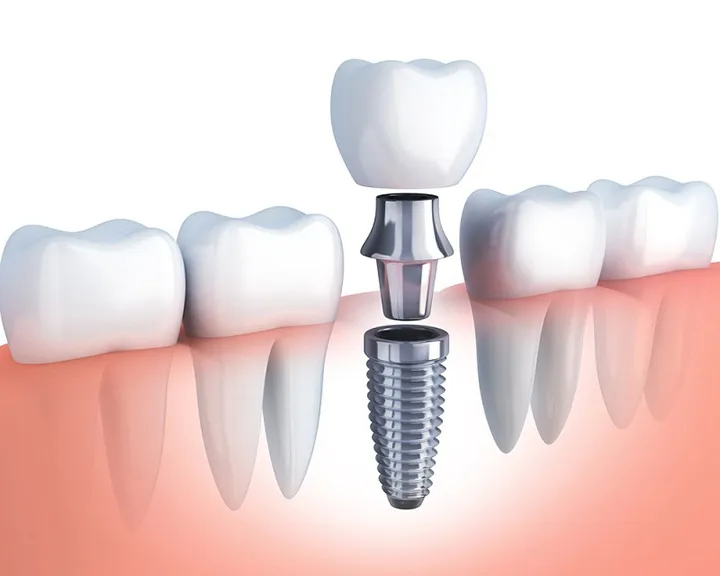

- Bọc răng sứ: Khi bị sâu răng nặng, có kèm tổn thương tủy, bác sĩ có thể chỉ định phương pháp bọc răng sứ. Trước tiên, bác sĩ sẽ điều trị tủy răng để ngăn chặn viêm nhiễm, sau đó mài răng và gắn mão sứ để bảo vệ răng và phục hồi chức năng.